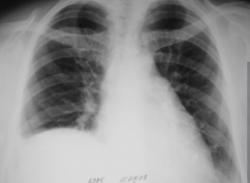

Оказывается во время операции был пересечен нерв. Вот рентгенограммы - 1 сделана после операции, вторая - через 1 месяц.

Ну уж коли за 10 мес. динамики нет, значит всё дело в релаксации диафрагмы, а выпота мало и обтурции бронхов, видимо, нет. Поджаты и уже не расправятся S4, S5, S7, S8, S9, S10.